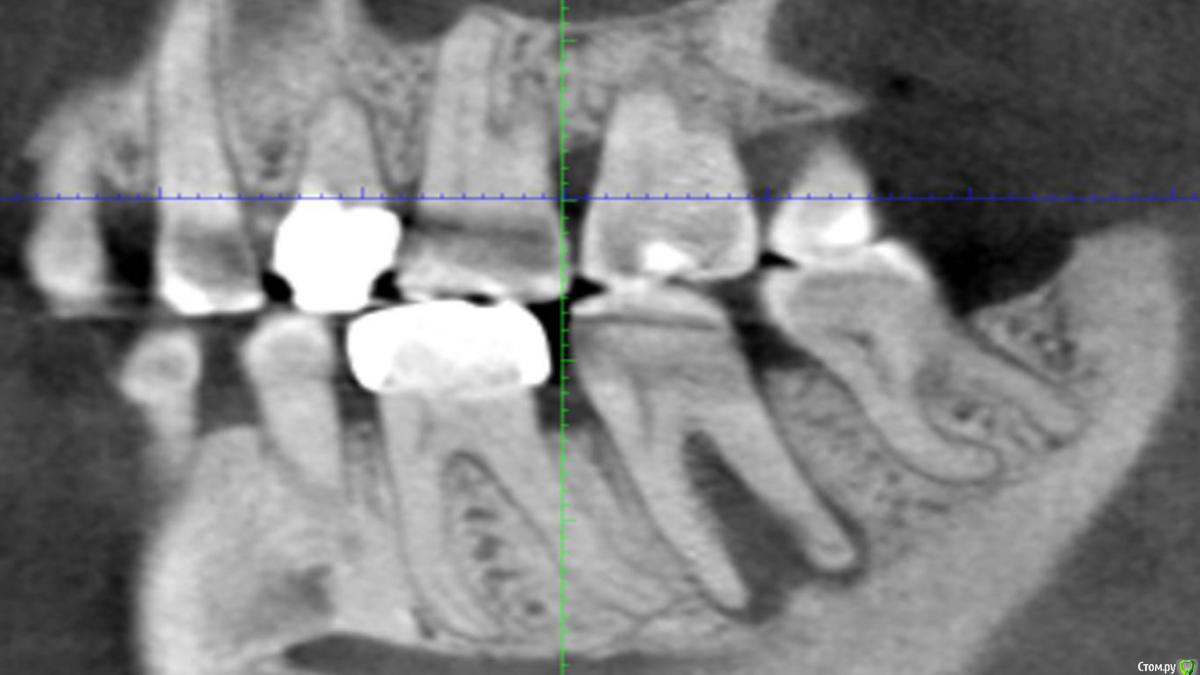

Сева северный Опубликовано 21 апреля, 2016 Поделиться Опубликовано 21 апреля, 2016 (изменено) .Хотелось бы выслушать мнение по зубу 4.6Пациент пришел по рекомендации, коллеги, из сторонней клиники. . Как бы вы поступили в данной ситуации? ( Скриншоты КТ, прилагаются) Изменено 21 апреля, 2016 пользователем Сева северный Ссылка на комментарий

Сева северный Опубликовано 21 апреля, 2016 Автор Поделиться Опубликовано 21 апреля, 2016 (изменено) Мужчина. Возраст: около 50,Жалобы. на болевые ощущения ..отсутствуют. Зуб ранее лечен, имеется старая пломба с нарушенным прилеганием, по границам- кариес. Пальпация, перкуссия безболезненна, в области бифуркации при надавливании, появляется жидкость, желтоватого цвета. При зондировании зонд погружается в межкорневое пространство примерно на 15 мм. Изменено 21 апреля, 2016 пользователем Сева северный Ссылка на комментарий